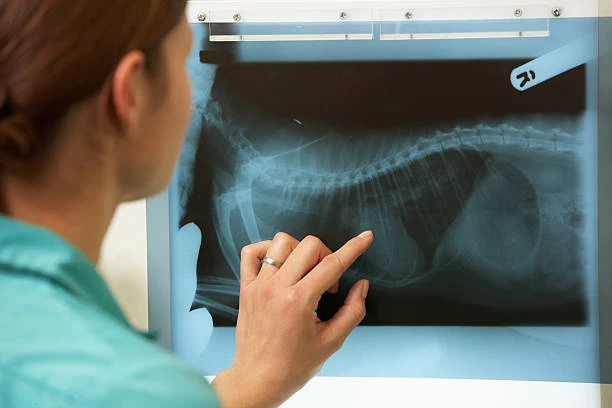

O procedimento de raio x para cachorro em hortolândia é realizado por profissionais capacitados e experientes, garantindo a segurança e conforto do animal durante o exame. O pet é posicionado adequadamente para a realização das imagens, que são captadas em questão de segundos.

A clínica veterinária RaçãoPet Saúde Animal conta com equipamentos de última geração para a realização de raio x, garantindo imagens nítidas e de alta qualidade para auxiliar no diagnóstico preciso das condições de saúde do seu animal de estimação.